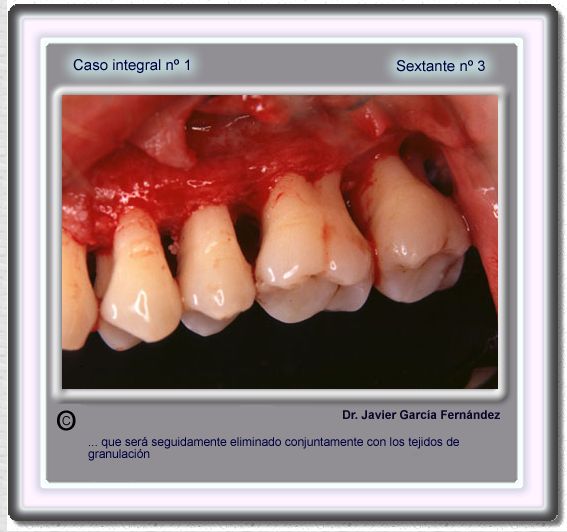

image 50